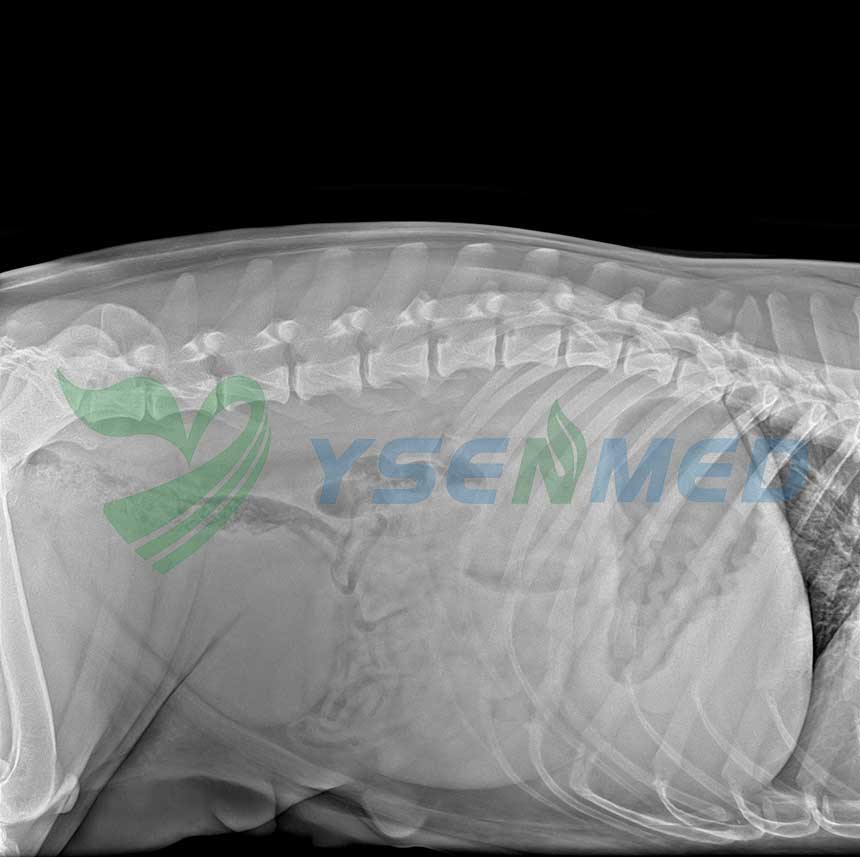

YSENMED YSDR-VET320 32kW veterinary digital x-ray system has just been set up in a Columbian vet clinic, and the vet is very satisfied with the image quality and our service.